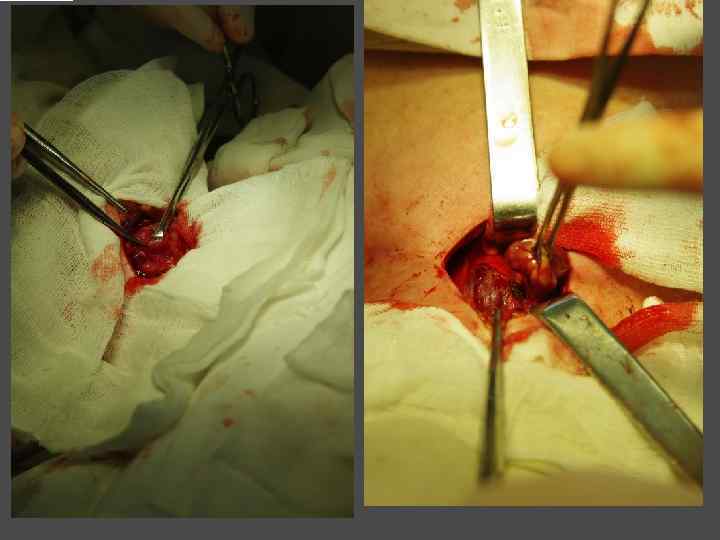

ВИДЫ ХИРУРГИЧЕКИХ ВМЕШАТЕЛЬСТВ ► Энуклеация ► Резекция щитовидной железы (доли) ► Тиреоидэктомия (гемитиреоидэктомия)

ХИРУРГИЧЕСКОЕ ЛЕЧЕНИЕ ЗОБА

ОСЛОЖНЕНИЯ ХИРУРГИЧЕСКОГО ЛЕЧЕНИЯ ►Поражение возвратного нерва, приводящее к параличу голосовой связки на стороне поражения, как следствие – изменение тембра голоса, сужение голосовой щели, затруднение дыхания. ► Кровотечение. ►Тиреотоксический криз. ► Гипопаратиреоз. ► Рецидив тиреотоксикоза. ► Формирование порочного рубца.